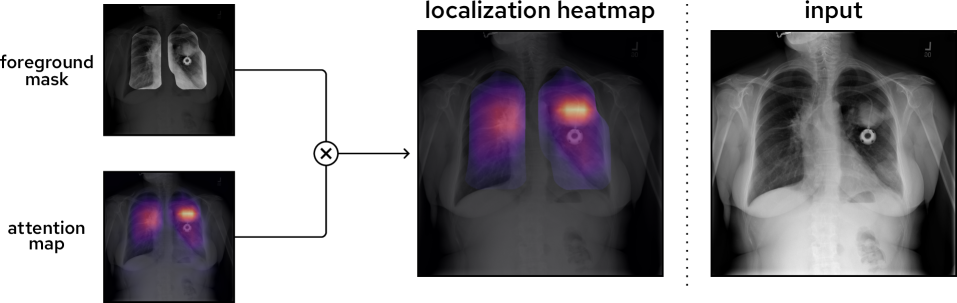

3.2.2 Heatmaps

During inference, localization heatmaps 𝜩(0,1)H×W×C\boldsymbol{\mathit{\Xi}}\in\left(0,1\right)^{H\times W\times C} are produced by fusing each class-specific foreground mask and attention map using element-wise multiplication:

𝜩(i,j,c)=𝑨(i,j,c)𝑺f(i,j,c)\boldsymbol{\mathit{\Xi}}^{\left(i,j,c\right)}=\boldsymbol{A}^{\left(i,j,c\right)}\thinspace\boldsymbol{S}_{\negthinspace f}^{\,\left(i,j,c\right)} (2)

where 𝜩(i,j,c)\boldsymbol{\mathit{\Xi}}^{\left(i,j,c\right)}: localization heatmap of class cc at index (i,j)\left(i,j\right), and 𝑺f(i,j,c)\boldsymbol{S}_{\negthinspace f}^{\,\left(i,j,c\right)}: foreground mask of class cc at index (i,j)\left(i,j\right).

Each foreground mask ensures that the localization heatmap is constrained to class-specific foreground regions. Additionally, the background suppression methodology (Sec.˜3.5.2) enforces a prior over potential locations of classes. The result is a highly precise localization of chest X-ray pathologies, which is seen in Fig.˜3 with regards to the large mass in the upper-middle region of the left lung.

Refer to caption

Figure 3: Weakly-supervised localization method of CLARiTy. During inference, a foreground mask and attention map are produced for each class. Element-wise multiplication yields a class-specific localization heatmap that is both highly precise and confined to the class’ ground truth region. In this example chest X-ray, a mass (round opacity) is found in the upper-middle left lung of the patient. The attention map has high intensity directly over the mass, and the heatmap intensity is confined to the lung lobes.